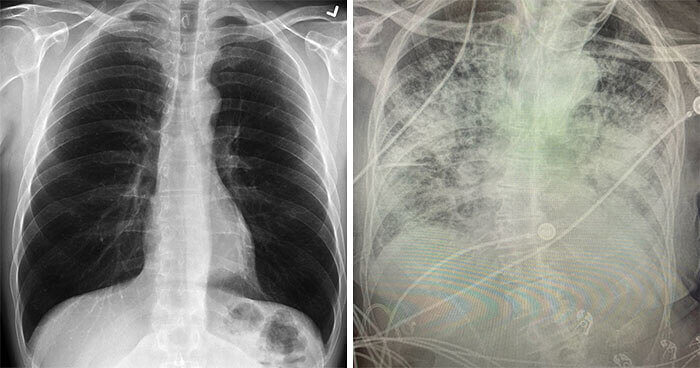

Normal Lungs Vs. COVID-19 Lungs Are Actually Pretty Shocking

It's been medical mayhem, but science is now starting to get a handle on the virus known as COVID-19. Everyone knows that it has the potential to affect the lungs, in severe cases. But just what does that look like from the inside?

At present, researchers have found that extreme cases of COVID-19 produce crazy scarring on the lungs. They believe it goes away over time, and heals better than cigarette damage. Only time will tell, of course. On the left, a regular set. On the right, corona!